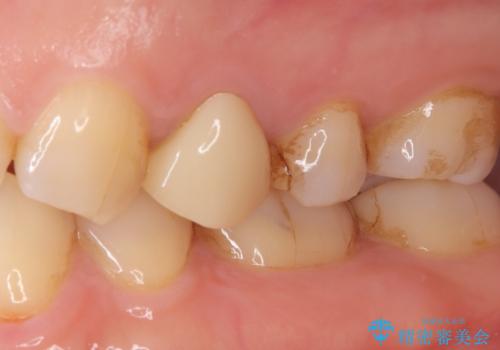

- 他院で昔に根管治療を行ったが、歯肉を押したときの痛みと普段の違和感が残ったままであることを主訴に来院されました。

以前治療した病院では、再根管治療を行わずに歯根端切除のみでの対応を進められたが、治療方針に納得できず当院を受診されました。

治療介入における意思決定が重要となるケースでしたが、患者と相談して①再根管治療→②外科的歯内療法という流れで治療を行いました。

再根管治療を優先した理由としては、破折診断と、当時の治療においてラバーダムや顕微鏡を使用してないとの話があったためです。

結果、根管内にはイスムスにデブリが多く見られたものの破折線は確認できませんでした。再根管治療後、症状の経過を3ヶ月ほど確認しましたが打診、違和感が消失しておらず、外科的歯内療法を行うこととなりました。